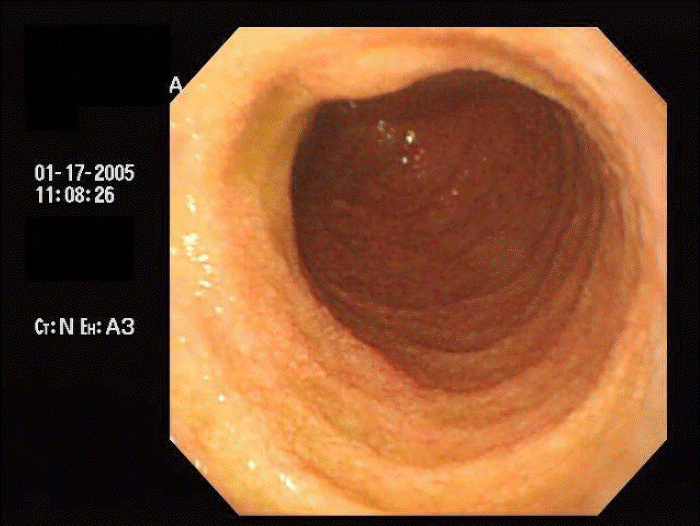

Figure 2.

Endoscopic exam revealed granular appearance of the mucosa in the second portion of duodenum, which is compatible with infiltrative disease of the duodenum.